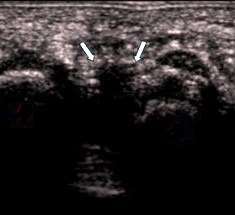

•Il est conseillé de mesurer le névrome selon ses 3 dimensions, sa largeur étant plus volontiers augmentée par rapport à son épaisseur et donc apparaissant la dimension la plus significative. Mon expérience personnelle, reposant sur un nombre important de cas suivis en pré et post-opératoire, m'incite à considérer que le nerf interosseux plantaire ne doit pas dépasser à l'état normal 1,6 mm d'épaisseur (habituellement sur une coupe longitudinale, réalisée de préférence par abord plantaire avec manœuvre de Mulder mettant le nerf le plus parallèle possible à la sonde et donc le mieux démontrable).